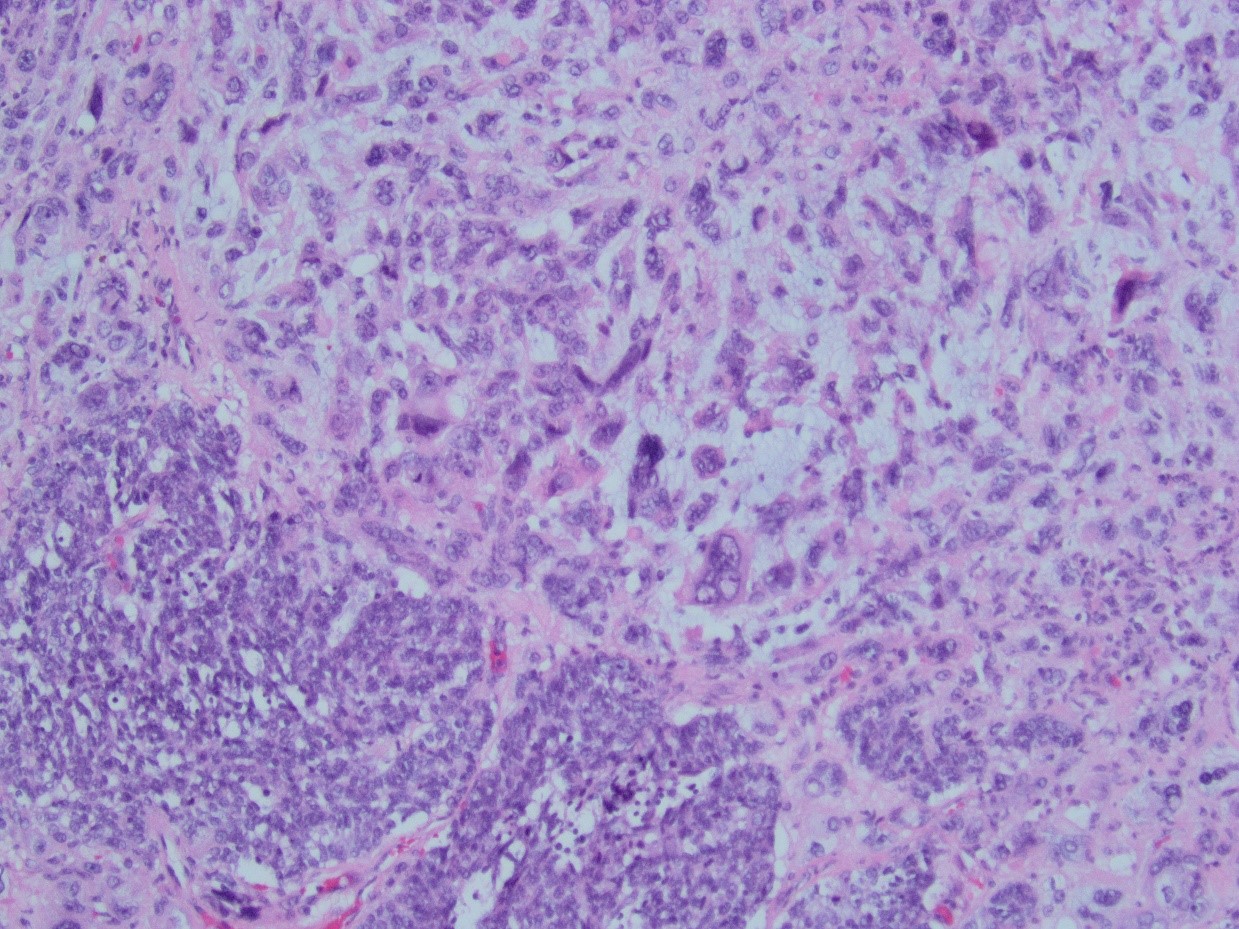

Answer: C. Mixed Mullerian tumor/carcinosarcoma. Sections from the tumor show biphasic, malignant tumor with high-grade epithelial and sarcomatous components consistent with carcinosarcoma.

Histopathology: The tumors are composed of an admixture of malignant epithelium and mesenchyme, which is typically sharply juxtaposed. The carcinomatous component often shows endometrioid or serous differentiation, but clear cell and undifferentiated carcinoma may be encountered. The mesenchymal component most commonly consists of high-grade sarcoma NOS, but heterologous elements (including rhabdomyosarcoma, chondrosarcoma, and rarely osteosarcoma) may be seen